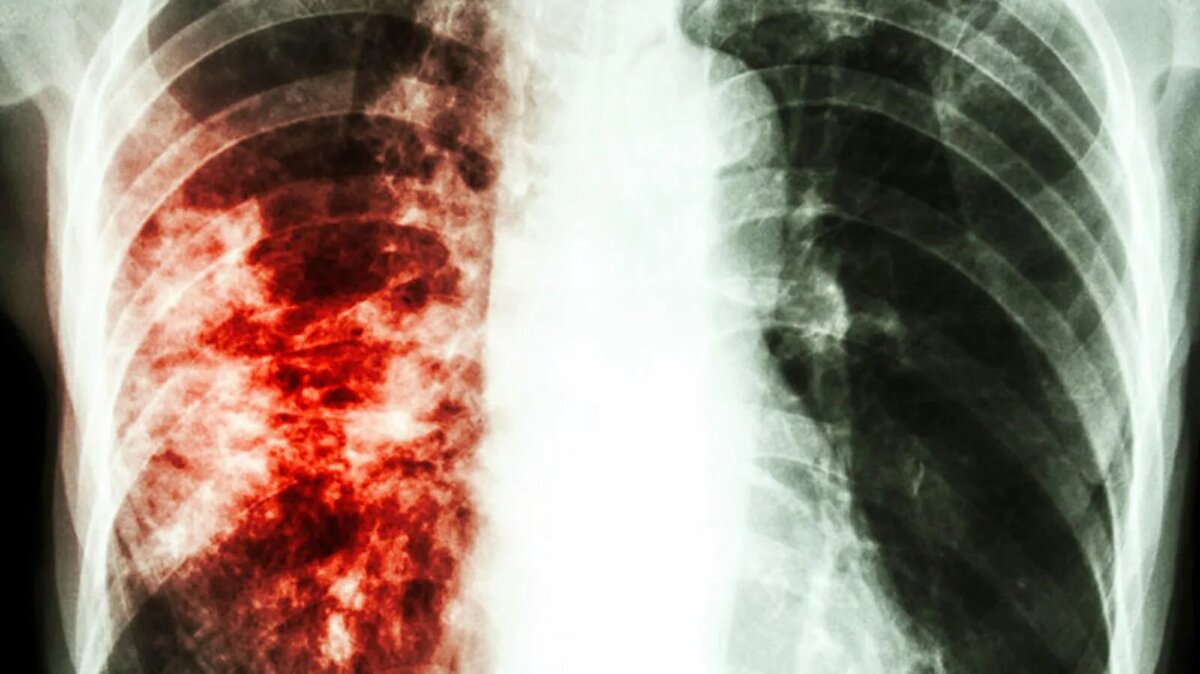

Как распознать туберкулез?

Среди основных симптомов можно выделить длительный кашель, который может длиться более 2-3 недель, иногда с кровью. Также повышенная температура более 37°C. И наконец, потливость, слабость, потеря веса без видимых на то причин.

Важно! На ранних стадиях туберкулез может протекать бессимптомно. Единственный надежный способ выявить болезнь – флюорография или анализ мокроты.